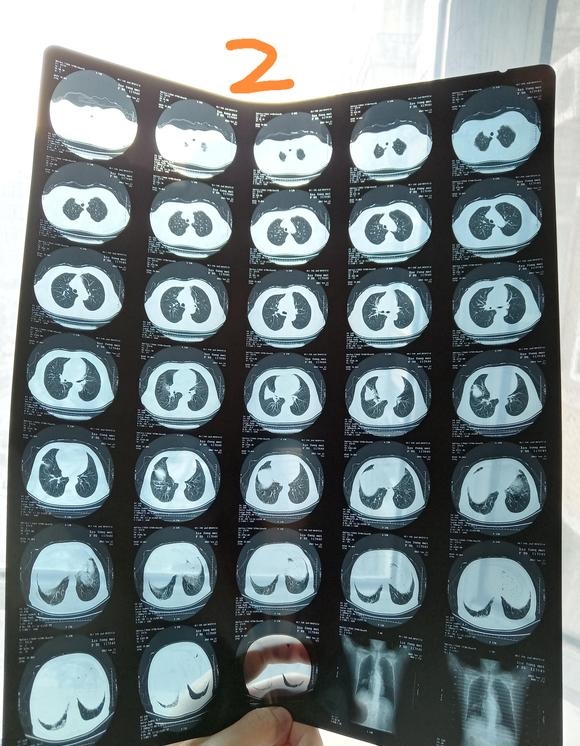

北港永下 02021-12-21 患者家属我父亲体检时发现有肿块。到人民医院检查结果显示食管囊肿或支气管囊肿本来医生说不是很大的手术。几天前做了增强ct。又说有可...